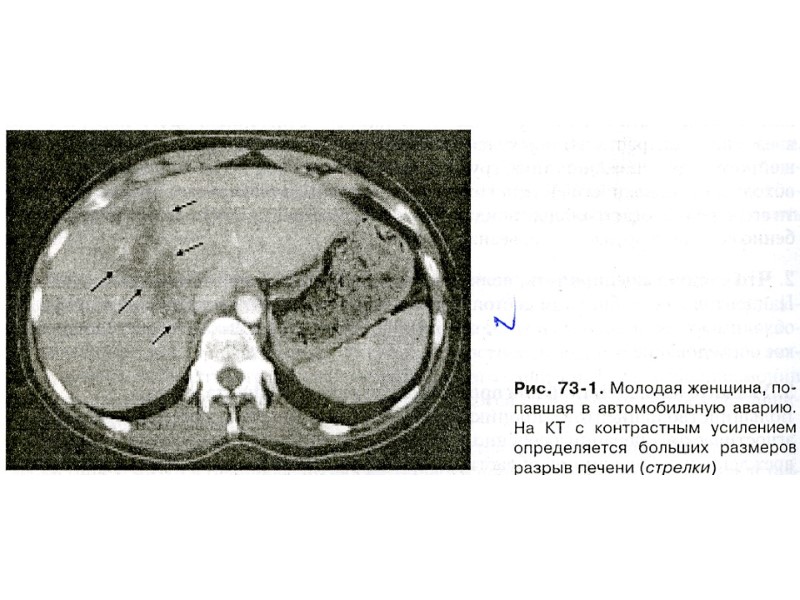

ОСТЕОДЕСТРУКЦИЯ Рентгенограмма бедра и области коленного сустава Остеодеструкция при остеомиелите